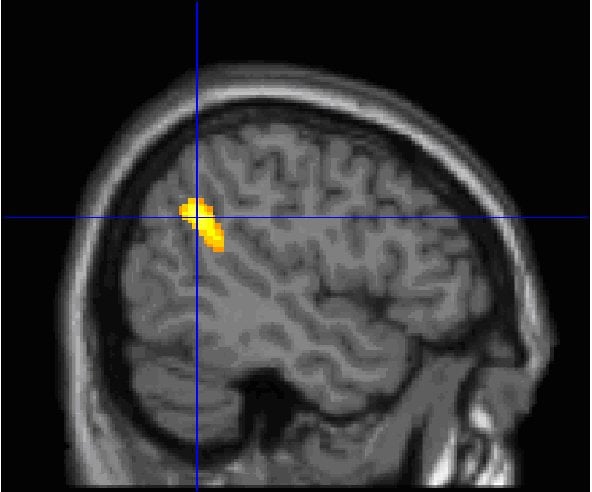

In a study published in the journal Neuropsychopharmacology, the researchers show that the temporoparietal junction, an information-processing hub in the brain, is more active in high dream recallers. Increased activity in this brain region might facilitate attention orienting toward external stimuli and promote intrasleep wakefulness, thereby facilitating the encoding of dreams in memory.

In this new study, the research team sought to identify which areas of the brain differentiate high and low dream recallers. They used Positron Emission Tomography (PET) to measure the spontaneous brain activity of 41 volunteers during wakefulness and sleep. The volunteers were classified into 2 groups: 21 “high dream recallers” who recalled dreams 5.2 mornings per week in average, and 20 “low dream recallers,” who reported 2 dreams per month in average. High dream recallers, both while awake and while asleep, showed stronger spontaneous brain activity in the medial prefrontal cortex (mPFC) and in the temporoparietal junction (TPJ), an area of the brain involved in attention orienting toward external stimuli.

The South African neuropsychologist Mark Solms had observed in earlier studies that lesions in these two brain areas led to a cessation of dream recall. The originality of the French team’s results is to show brain activity differences between high and low dream recallers during sleep and also during wakefulness.